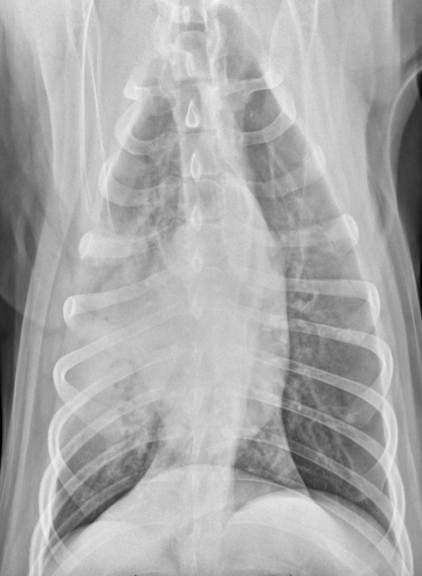

18

Q

Lung Pattern?

A

Alveolar

Air bronchogram